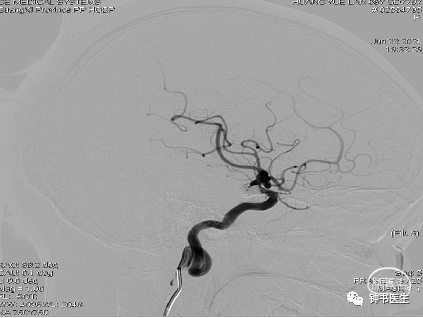

2021-06-22 DSA

R-ICA